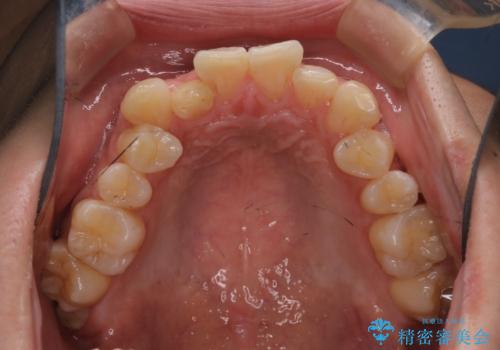

前歯のガタガタを治したい。

- 凸凹を治したいと来院された患者様です。

インビザラインにて、遠心移動を行いながら綺麗に配列することができました。